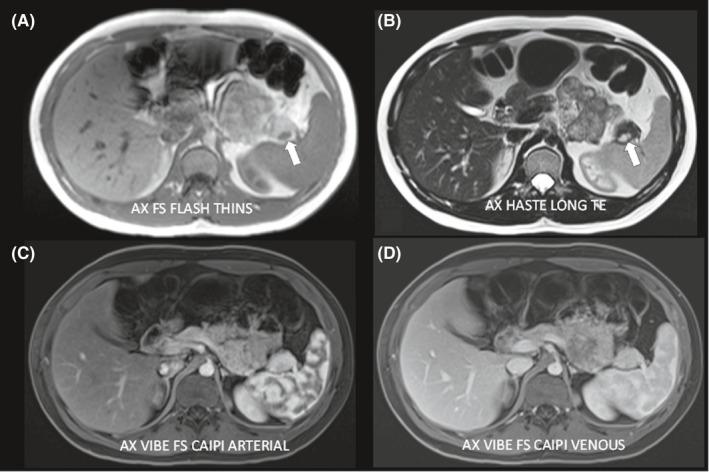

Hypoglycemia secondary to insulinoma masking the onset of type 1 diabetes in an adolescent.

Type 1 diabetes and insulinoma can co-occur in pediatric patients and may present with episodes of hypo- and hyperglycemia, significant glycemic variability, and weight gain. Surgical resection leads to development of fulminant diabetes.